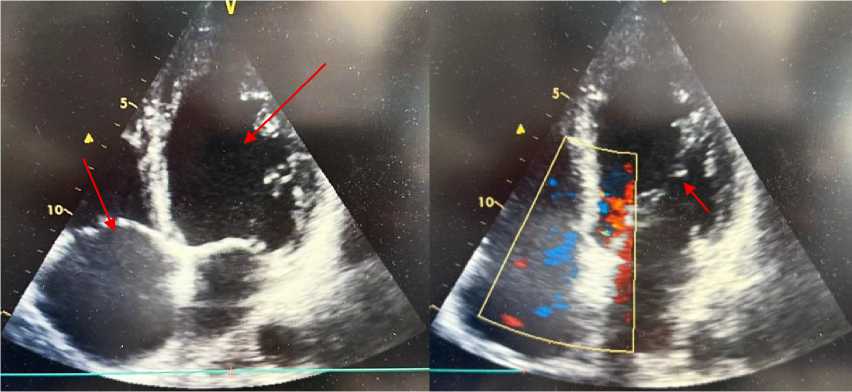

Эхокардиография. По данным ультразвукового исследования сердца у пациента А., 38 лет: толщина межжелудочковой перегородки — 0,9 см, задней стенки левого желудочка (ЛЖ) — 0,9 см. Фракция выброса ЛЖ (по Симпсону) — 38%. Размер левого предсердия — 4,5 см. Конечный систолический размер ЛЖ — 4,2 см, конечный диастолический размер ЛЖ — 6,1 см. Конечный систолический объём ЛЖ — 72 мл (референс: 18–68 мл), конечный диастолический объём ЛЖ — 168 мл (референс: 59–157 мл). Размер правого желудочка — 2,2 см, толщина его передней стенки — 0,4 см. Систолическое давление в лёгочной артерии — 32 мм рт. ст. Выявлены диффузный гипокинез миокарда ЛЖ, снижение систолической функции и нарушение процессов диастолического расслабления. Полости левых отделов сердца расширены. Перикард — без патологических изменений (Рисунок 2, 3, 4). Отмечены признаки атеросклеротического поражения аорты, аортального и митрального клапанов. Допплерографическое ультразвуковое исследование сонных и бедренных артерий: кровоток сохранён, признаков структурных и функциональных нарушений не выявлено. При обследовании венозных сосудов верхних и нижних конечностей тромбоз не диагностирован.

Рисунок 4. Эхокардиография пациента А., 38 лет с миокардитом. Парастернальная позиция, короткая ось на уровне митрального клапана